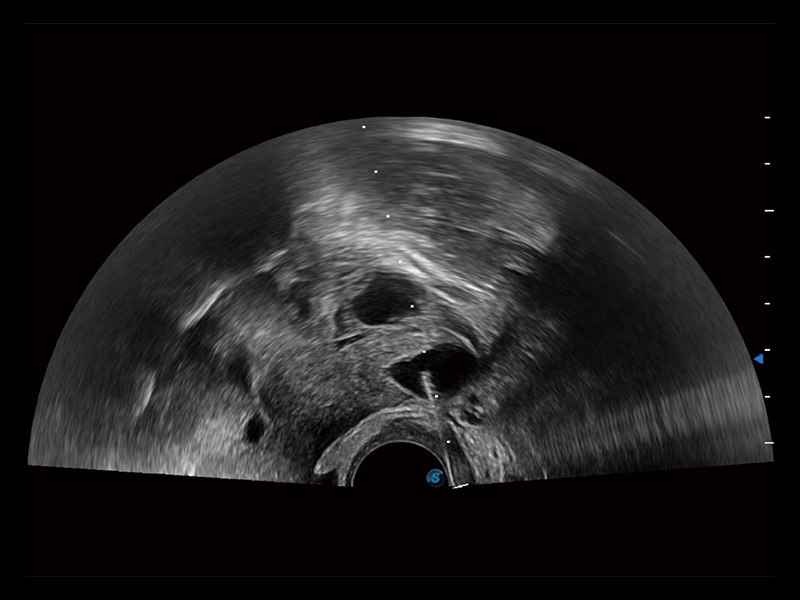

超声引导下双侧卵巢穿刺取卵